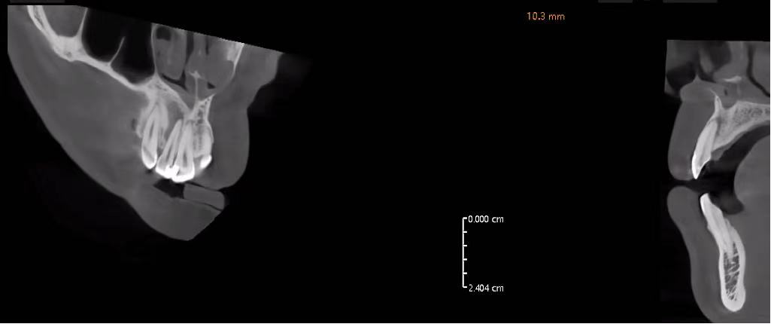

CBCT reveals a large ill-defined radiolucent lesion at the apex of #12

12/29/2024: Follow-up visit: Improved soreness, weakness and softness with mastication. CBCT demonstrated decreased size of apical radiolucency in #12.

The CBCT scans demonstrate the resolution process of periapical inflammation in tooth 12. Over a period of more than four months, the periapical inflammation has essentially subsided, and bone regeneration has initiated in the regions with bone defects caused by the prior inflammation.